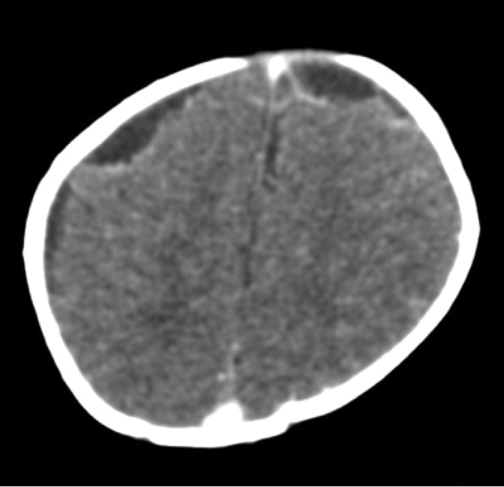

Based on this situation, concomitant treatment with phenytoin at a dose of 5 mg/kg/day was indicated; meropenem was restarted and control cultures in blood, CSF and urine were taken. CSF control studies reported hypoglycorrhachia and hyperproteinorrachia within the ranges of bacterial meningitis, with fluctuating values of polymorphonuclear and leukocytes (Table 2). After 10 days of antibiotic treatment, a control simple and contrastig brain CT was performed, which reported meningeal vascular reinforcement and right frontotemporal and left frontal subdural effusions, consistent with clinical findings of acute meningitis (Figure 1). Nevertheless, due to clinical deterioration, the possibility of nosocomial gram-positive bacterial coinfection by germs was considered, so vancomycin was added to the antibiotic treatment at a dose of 60 mg/kg/day. Vancomycin was suspended five days later, after 72 hours without fever, within th context of negative control blood cultures, urine culture and CSF culture.

Figure 1. Simple and contrasting control CAT scan on the 10th day of antibiotic treatment. Source: Own elaboration based on the data obtained in the study.